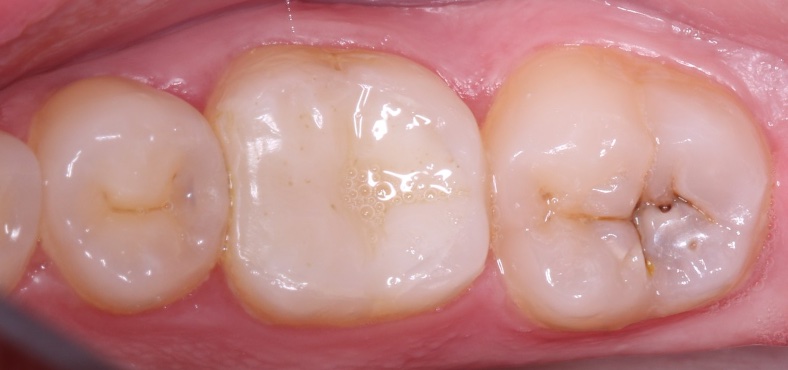

Наши работы